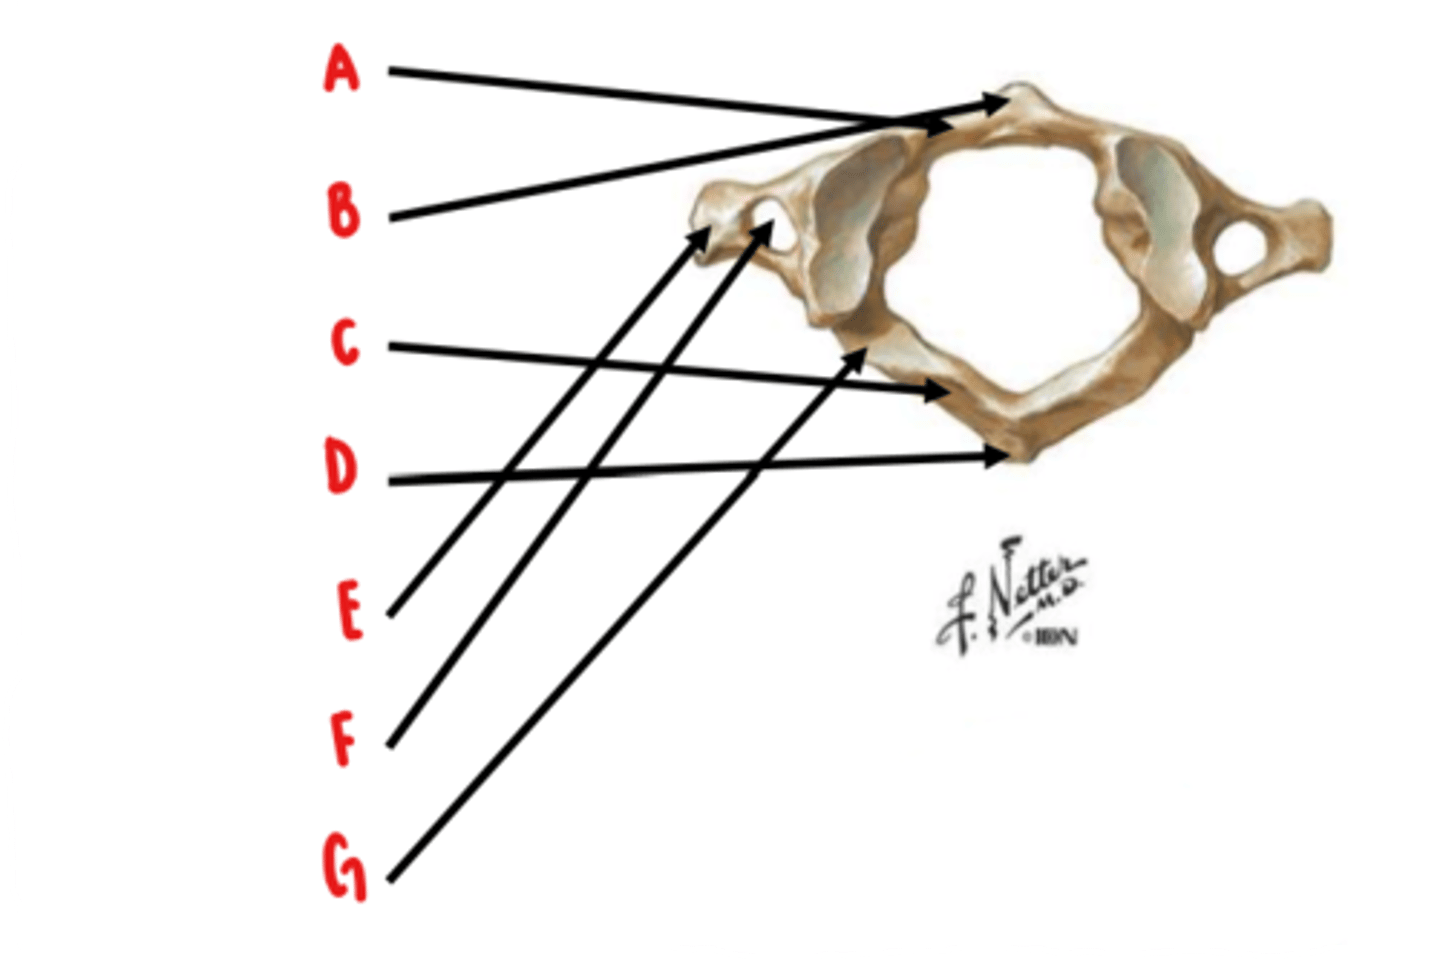

Atlas (C1)

What vertebrae is this?

anterior arch

Identify A

anterior tubercle

Identify B

posterior arch

Identify C

posterior tubercle

Identify D

transverse process

Identify E

transverse foramen

Identify F

groove for vertebral artery

Identify G